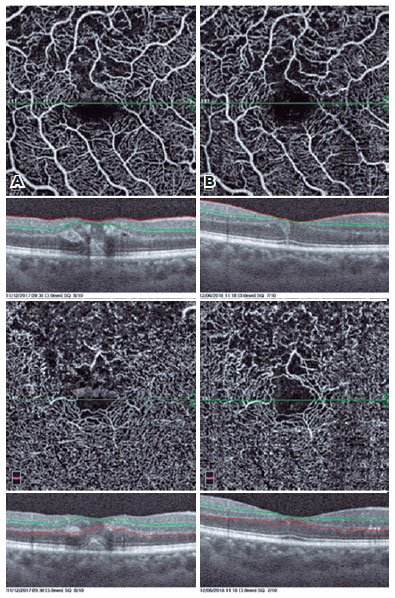

In addition, the cystic structures, especially those in the deep vascular layer, were stretched to a great extent in OCTA images. The perifoveal capillary arcade improved remarkably after the treatment (Figures 1-4).

In our study, we evaluated our patients with both FFA and OCTA before and after treatment, and we were able to evaluate the microvascular changes in both the SCP and DCP with OCTA. We determined recovery of perifoveal vascular arcade, regression of cysts, improvement in capillary network, and reductions in nonperfusion areas.

The capillaries could be displaced at the periphery of the cysts as mentioned by Couturier et al.(13). An increase in vascular density may be caused by the regression of the cysts after treatment. In our study, we found an increase in parafoveal vessel density after treatment. This is probably due to the cysts being stretched and the emergence of the underlying intact capillary bed.